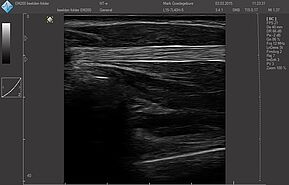

Датчики имеют большую чувствительность и высокое разрешение, благодаря чему обеспечивают максимальное проникновение и улучшают соотношение сигнал /шум. В результате формируется максимально четкая детализированная картинка УЗИ изображения.

- Усовершенствованная технология уменьшения спекл-шумов

- Улучшение изображения